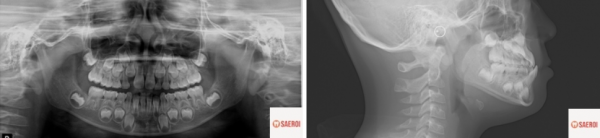

d1d86fa678bc9afe4b079fc3bd0a6047_1743648027_5832.png

파노라마 사진상에서 치아 맹출 공간이

부족해 보이는 것을 알 수 있으며

/

측면 엑스레이에서는

거꾸로 물리는 앞니가 명확히 관찰됨과 동시에

위턱의 저성장과 아래턱의 과성장으로 인해 발현된

주걱턱 모습을 확인할 수 있습니다.